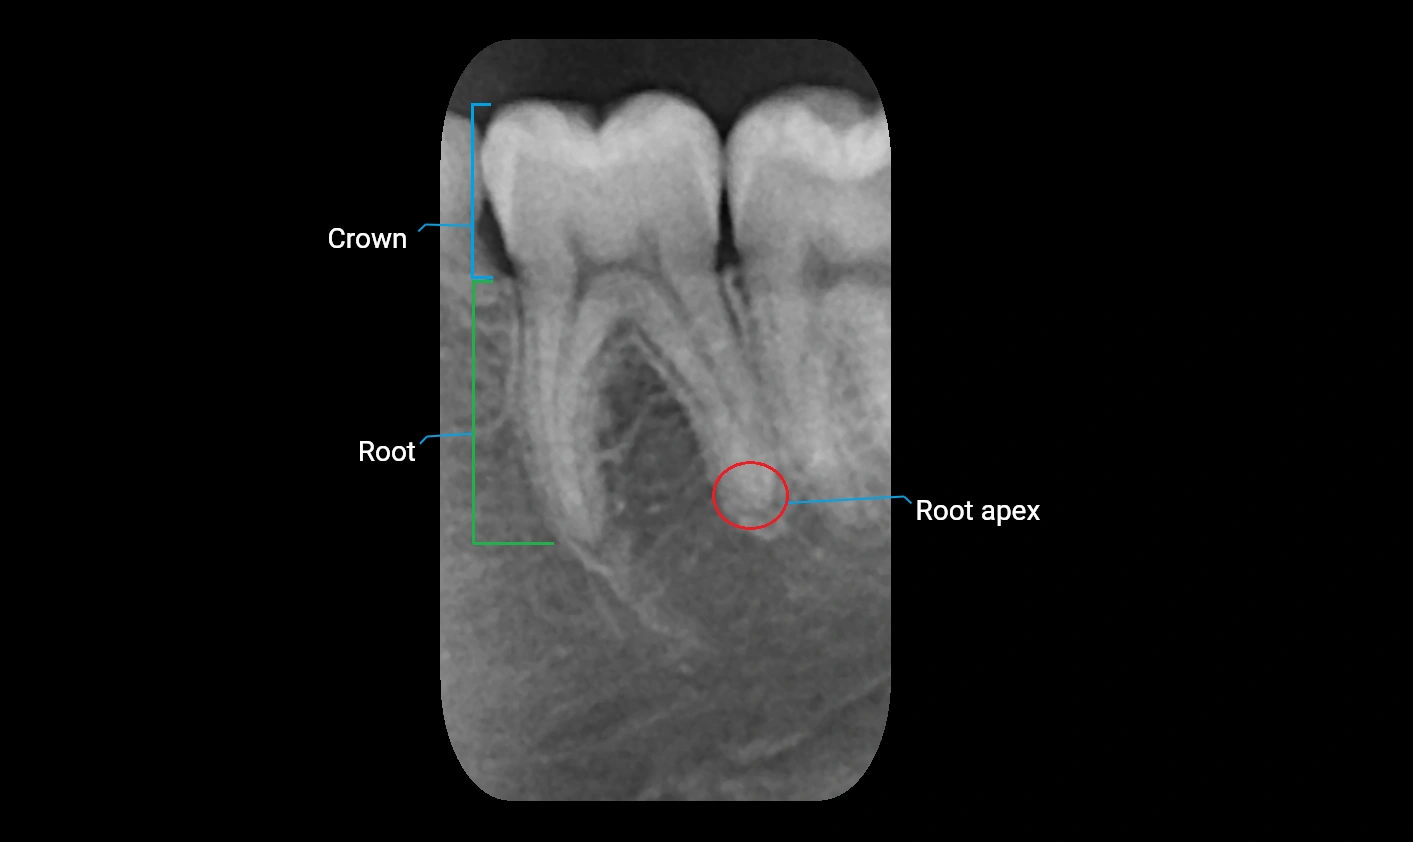

MRI Appearance

T1-weighted images:

• Cortical bone appears low signal (hypointense), while the trabecular bone is slightly higher signal due to marrow fat

• Surrounding soft tissues and subcutaneous fat appear hyperintense, creating natural contrast

• Dental alveoli may appear as small, well-demarcated hypointense cavities

• Pathology, such as cysts or inflammatory lesions, appears hyperintense or alters normal bone signal

T2-weighted images:

• Cortical bone remains hypointense

• Marrow and soft tissues appear hyperintense, making edema, cystic changes, or infection more conspicuous

• Useful for evaluating bone marrow pathology or early inflammatory changes